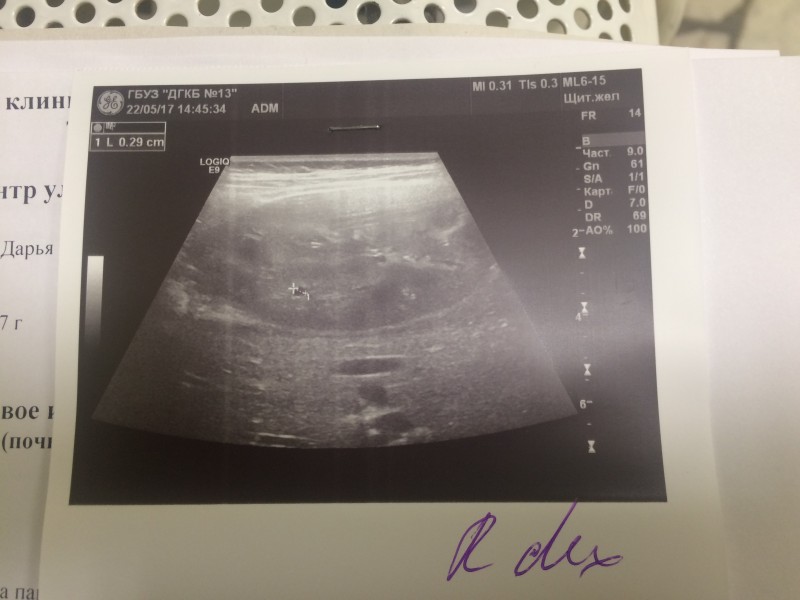

Пробегали от участковых врачей, до специалистов в Филатовской. Пока бегали, сдвали постоянно анализы и делали УЗИ. Итоги не ясны.

ещё. А файлы .pdf не могу выложить - пишет, недопустимый формат. Там анализы крови и мочи: 22/04/17 - белок в моче - 0,164 24/04/17 - белок в моче - 0,265 27/04/17 - клинический анализ крови: Нейтрофилы(общ.число), % 38.3, Лимфоциты, % 50.8, креатинин 51, мочевина 3,6

У дочки всё в порядке. Возвращаюсь к истории сына. Все анализы в норме, но одна киста выросла до 4 см в диаметре. Специалисты Филатовской больницы решили её склерозировать, учитывая удобное прилежание. Назначили госпитализацию на 4 февраля. 5-го КТ перед операцией, потом сама операция. Надеются убирать "проколом". Интересовался ваптанами. Ценник во всех странах отличается на 1-2 Евро... Неподёмный пока для нас, учитывая, что и "побочка" у препаратов есть, не кислая.

Операцию временно отложили на пару дней. По результатам КТ решили две кисты склерозировать после пунктирования, а одну иссекать лапороскопически.